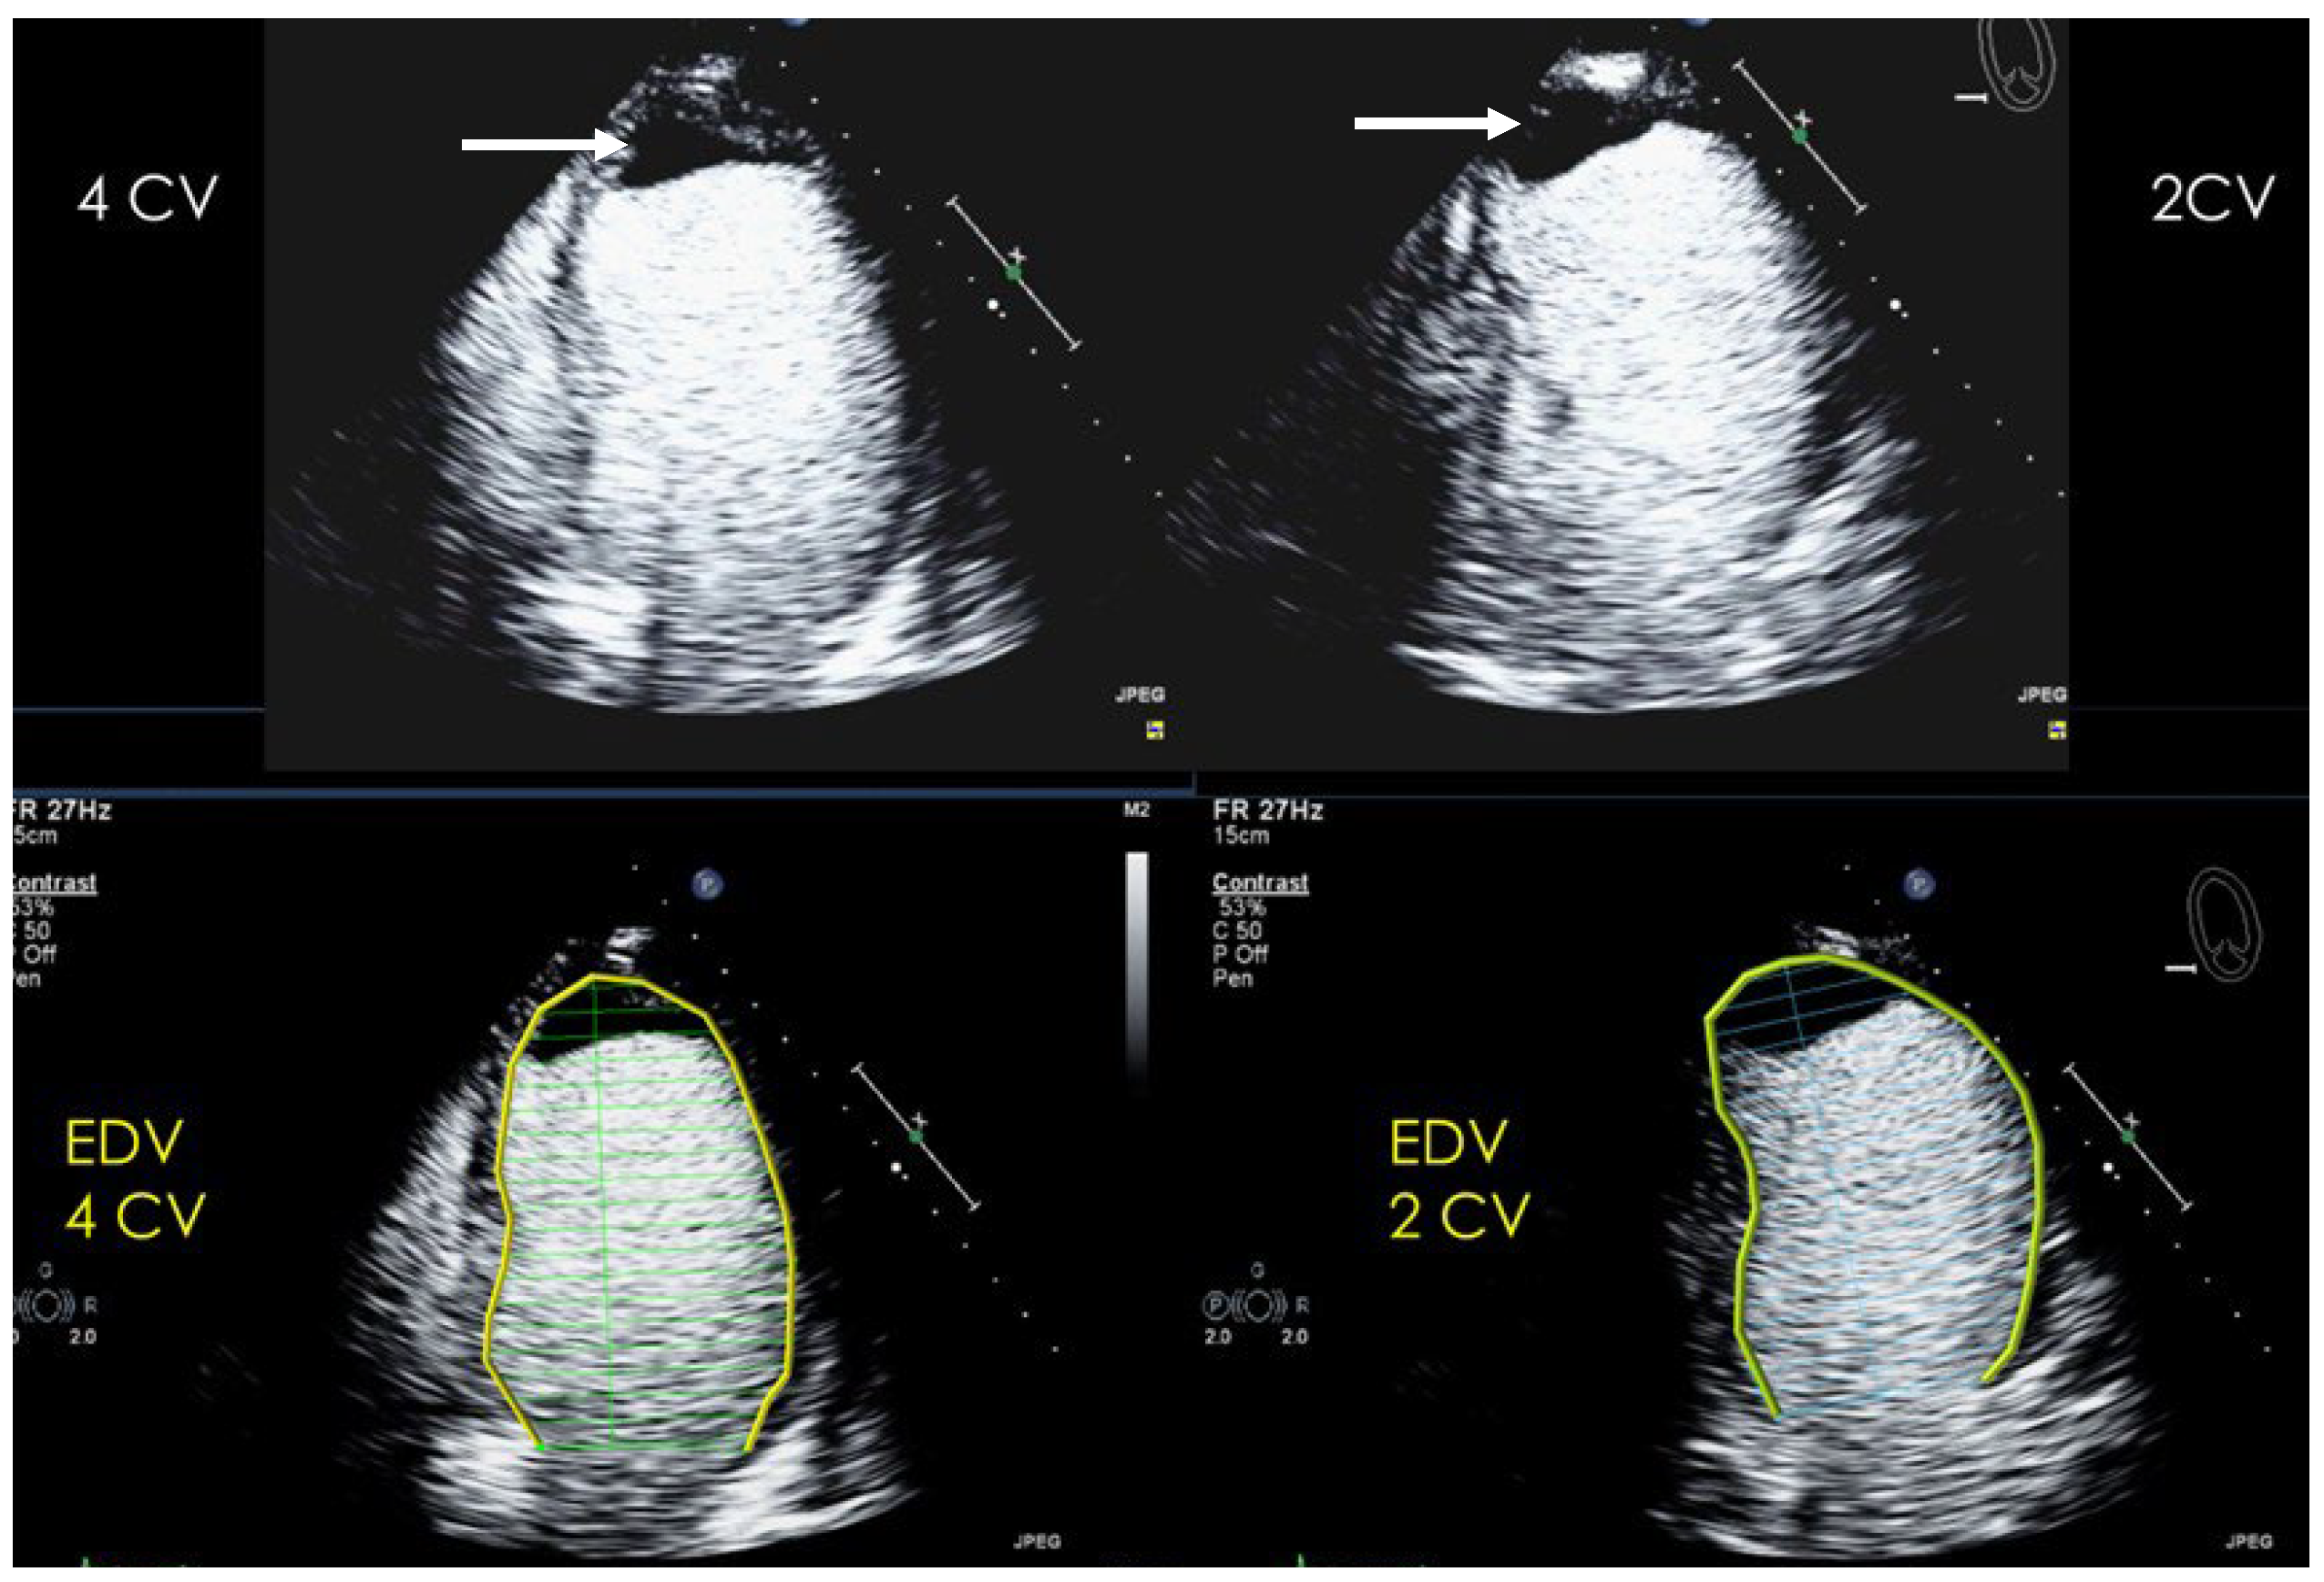

2.2.2. Pre-Assessment and Primary Scan Planes

| Imaging planes | Standard apical views, zoomed apical views and modified/zoomed views |

| Sector depth/width | First assessment of the global and regional function using low-MI method and display of the entire LV + 1/3 LA, then zoomed views to display the region of the aneurysm |

| Focus | At the depth of the aneurysm |

| Gain | Adjust to avoid obscuring the LV borders by intensive opacification of the cavity |